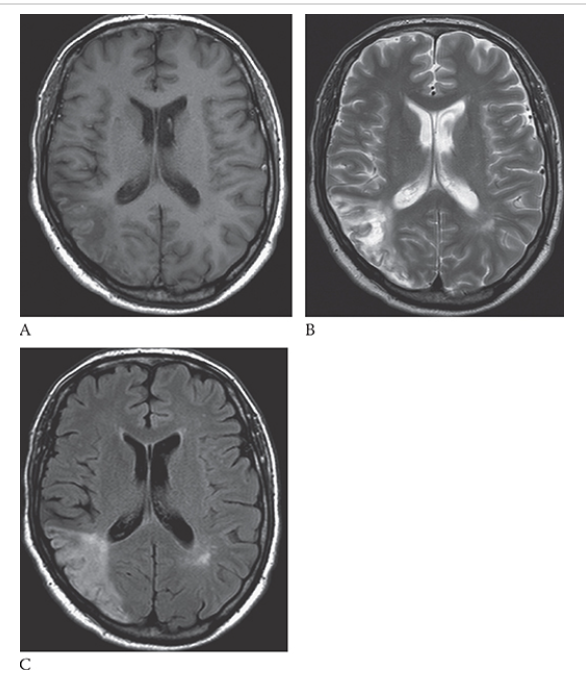

What is A

Ischemic Stroke. Axial T1W image shows an area of low signal in the white matter and increased signal of the gray matter in the right posterior parietal lobe. An axial T2W image

What is B

Ischemic Stroke. Axial T1W image shows increased signal in this area consistent with edema. FLAIR

What is C

Ischemic Stroke. Axial T1W image shows increased signal in the white and gray matter in this region.